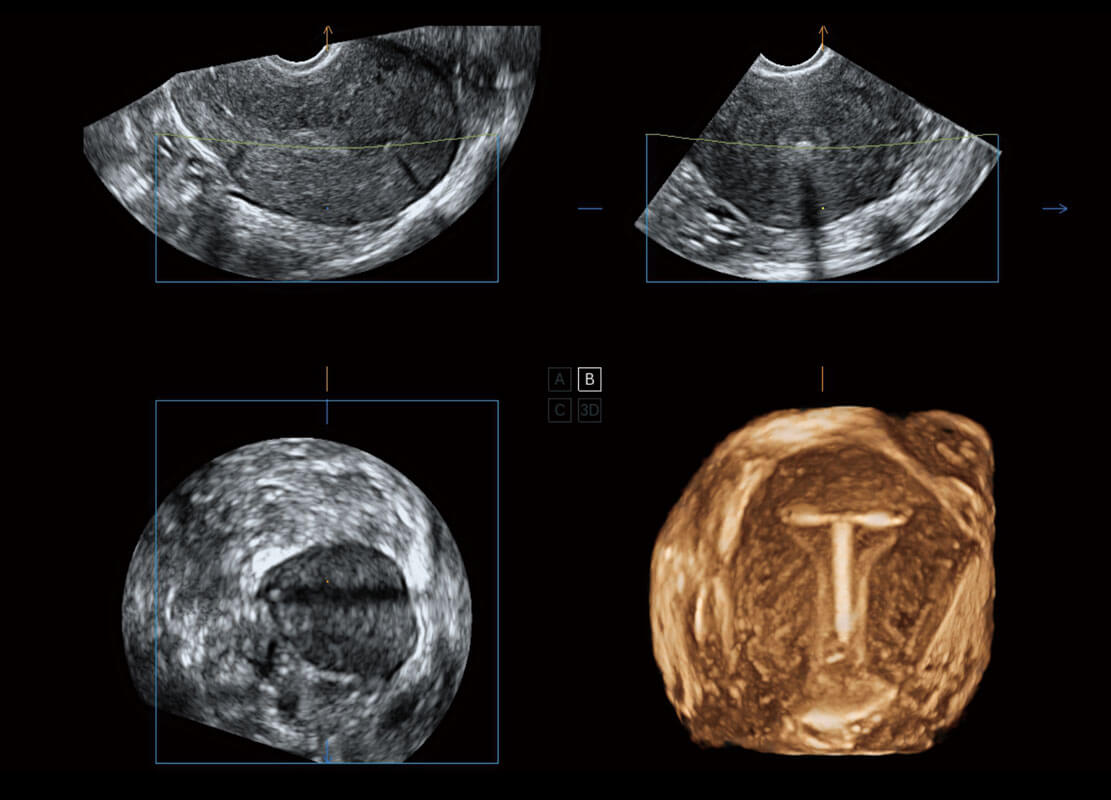

• 腔内三维-宫内节育器

盆底超声

P60为盆底超声检查提供应用方案,多种腔内及腹部容积探头提供从二维、三维到四维的优异图像品质,实时快速三维容积数据获取,专业的测量工具包等人性化设计,为超声医生诊断提供有力保障。

S-Pelvic

能够简化盆底检查的操作流程,可在二维模式及三维成像模式下实现一键自动提取出标准切面、自动识别当前切面、自动测量,提升盆底检查的高效性,同时也能让青年医生快捷的获得准确的检查结果。